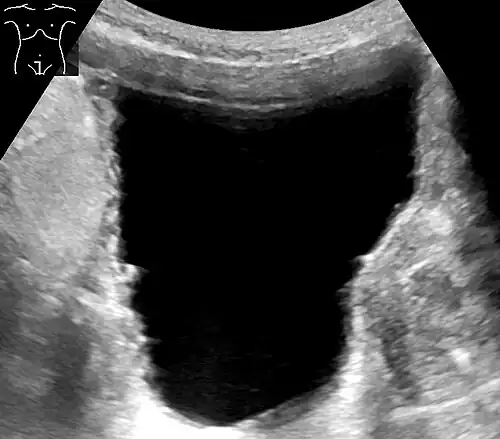

Ultrasound of the urinary bladder of an 85-year-old man. It shows a trabeculated wall, which is a sign of urinary retention.

Ultrasound – sound waves are used to visualize the kidneys and urinary bladder, assess the capacity of the bladder before voiding, and the remaining amount of urine after voiding. This helps know if there's a problem in emptying.